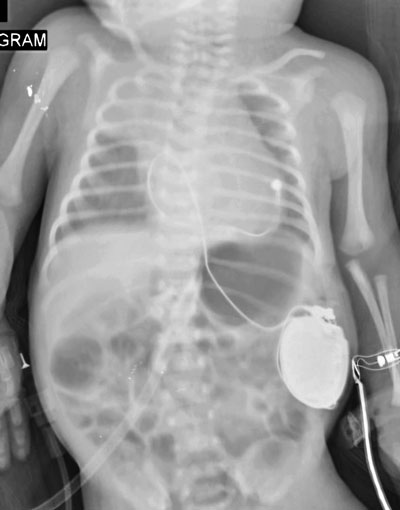

RS Awal Bros Batam Catat Sejarah Medis

Sukses Pasang Alat Pacu Jantung pada Bayi Baru Lahir